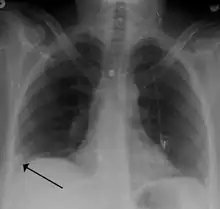

- Chest X-rays are often done on people with shortness of breath to help rule-out other causes, such as congestive heart failure and rib fracture. Chest X-rays in PE are rarely normal,[68] but usually lack signs that suggest the diagnosis of PE (for example, Westermark sign, Hampton's hump).